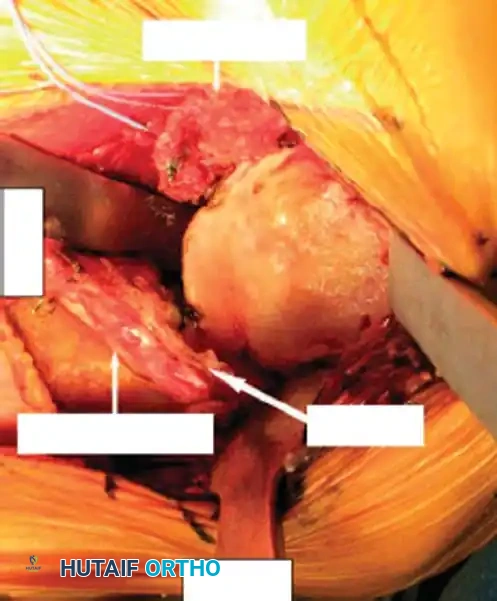

4. Glenoid Preparation

Excellent exposure is critical. Release the inferior capsule completely from the glenoid rim.

* Identify the center point of the glenoid.

* Perform concentric reaming to correct version and create a bleeding bone bed.

* Pitfall: Avoid excessive reaming, which penetrates the dense subchondral bone plate and enters the weaker cancellous vault, leading to catastrophic early subsidence.

Cement the all-polyethylene glenoid component using pulsatile lavage, meticulous drying, and pressurization techniques.